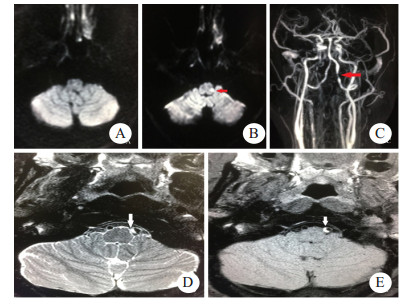

| A:首次磁共振检查DWI阴性;B:半年后复诊T2WI可见右侧延髓软化灶;C:首次头颅CTA可见左侧椎动脉线珠样改变(箭头示);D:半年后复查CTA椎动脉夹层愈合 图 1 例1患者影像学检查结果 |

1 资料与方法患者1,男性,29岁,因“后颈部疼痛3 d,眩晕、吞咽困难2 h”就诊急诊。患者3 d前无明显诱因下出现后颈部胀痛,疼痛持续性,2 h前出现眩晕,吞咽困难,流涎,持续无好转,无复视,无耳鸣及听力减退,无肢体瘫痪,无大小便障碍。既往体健,否认遗传病及传染病史,否认外伤及药物滥用。查体:意识清楚,口齿不清,两侧瞳孔等大,对光反射存在,眼球活动自如,自发眼震,鼻唇沟对称,伸舌居中,口腔分泌物多,左侧咽反射迟钝,颈软,心律齐,四肢肌张力正常,四肢肌力Ⅴ级,左侧指鼻试验、跟膝胫试验不稳,交叉性感觉障碍,两侧病理征阴性。患者疑似急性脑血管病,不能确诊,故仍启动溶栓绿色通道,立即完善血常规、超敏C反应蛋白(CRP)、肝肾功能、血糖、凝血酶原时间(PT)、国际标准化比值(INR)、肌酶均提示正常范围。头颅CT平扫未见明显异常。头颅DWI未见明显异常。头颅CT血管造影(CTA)可见左侧椎动脉局部线珠样改变,考虑VAD。最后诊断Wallenberg综合征、VAD。当时患者仍为溶栓治疗时间窗内,将静脉溶栓事项充分告知,患者及家属未选择溶栓治疗,遂予以阿司匹林、阿托伐他汀、异丙嗪、奥美拉唑治疗,次日眩晕减轻,仍有吞咽困难,患者家属要求转入某大学附属医院,之后继续采用阿司匹林、阿托伐他汀等药物治疗,辅以康复锻炼。半年后来我院复诊,患者吞咽功能恢复,遗留肢体感觉障碍,头颅MRI可见延髓软化灶,颈部血管CTA提示夹层愈合。本病例资料的报道已获得患者知情同意。

例1患者急性起病,表现为眩晕,吞咽障碍,查体有自发性眼震、交叉性感觉异常、共济运动不稳,提示急性延髓病变,病变性质不明确。患者青年男性,且无明显脑血管病危险因素,发病前有颈部疼痛,为防止误诊、漏诊,立即完善头颅DWI和CTA检查。其中头颅CTA检查发现左侧VAD,为病灶责任血管,虽然DWI为阴性,仍然诊断急性延髓梗死。目前缺乏颈部动脉夹层所致缺血性脑卒中患者进行静脉溶栓的有效性和安全性方面的研究,部分研究提示发病4.5 h内运用rtPA静脉溶栓可能是安全的[8-9]。本例患者及家属均未选择溶栓治疗方案,采用阿司匹林、阿托伐他汀治疗,所幸患者病情未进一步进展加重。